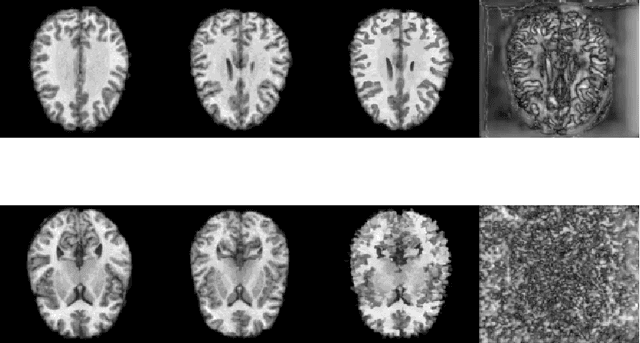

Abstract:The ability to reconstruct high-quality images from undersampled MRI data is vital in improving MRI temporal resolution and reducing acquisition times. Deep learning methods have been proposed for this task, but the lack of verified methods to quantify the uncertainty in the reconstructed images hampered clinical applicability. We introduce "NPB-REC", a non-parametric fully Bayesian framework, for MRI reconstruction from undersampled data with uncertainty estimation. We use Stochastic Gradient Langevin Dynamics during training to characterize the posterior distribution of the network parameters. This enables us to both improve the quality of the reconstructed images and quantify the uncertainty in the reconstructed images. We demonstrate the efficacy of our approach on a multi-coil MRI dataset from the fastMRI challenge and compare it to the baseline End-to-End Variational Network (E2E-VarNet). Our approach outperforms the baseline in terms of reconstruction accuracy by means of PSNR and SSIM ($34.55$, $0.908$ vs. $33.08$, $0.897$, $p<0.01$, acceleration rate $R=8$) and provides uncertainty measures that correlate better with the reconstruction error (Pearson correlation, $R=0.94$ vs. $R=0.91$). Additionally, our approach exhibits better generalization capabilities against anatomical distribution shifts (PSNR and SSIM of $32.38$, $0.849$ vs. $31.63$, $0.836$, $p<0.01$, training on brain data, inference on knee data, acceleration rate $R=8$). NPB-REC has the potential to facilitate the safe utilization of deep learning-based methods for MRI reconstruction from undersampled data. Code and trained models are available at \url{https://github.com/samahkh/NPB-REC}.

Abstract:Uncertainty quantification in deep-learning (DL) based image reconstruction models is critical for reliable clinical decision making based on the reconstructed images. We introduce "NPB-REC", a non-parametric fully Bayesian framework for uncertainty assessment in MRI reconstruction from undersampled "k-space" data. We use Stochastic gradient Langevin dynamics (SGLD) during the training phase to characterize the posterior distribution of the network weights. We demonstrated the added-value of our approach on the multi-coil brain MRI dataset, from the fastmri challenge, in comparison to the baseline E2E-VarNet with and without inference-time dropout. Our experiments show that NPB-REC outperforms the baseline by means of reconstruction accuracy (PSNR and SSIM of $34.55$, $0.908$ vs. $33.08$, $0.897$, $p<0.01$) in high acceleration rates ($R=8$). This is also measured in regions of clinical annotations. More significantly, it provides a more accurate estimate of the uncertainty that correlates with the reconstruction error, compared to the Monte-Carlo inference time Dropout method (Pearson correlation coefficient of $R=0.94$ vs. $R=0.91$). The proposed approach has the potential to facilitate safe utilization of DL based methods for MRI reconstruction from undersampled data. Code and trained models are available in \url{https://github.com/samahkh/NPB-REC}.